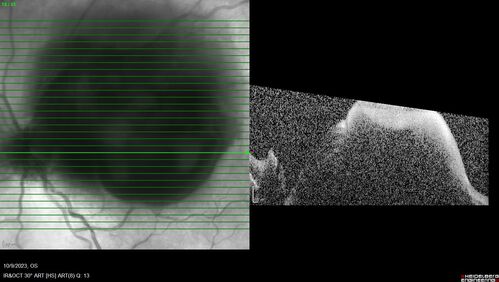

Ruptured Retinal Arterial Macroaneurysm - Submacular hemorrhage and BRAO

81 year old female with vision loss for a few days. Coumadin was high with INR at 3.1 VA 6/200